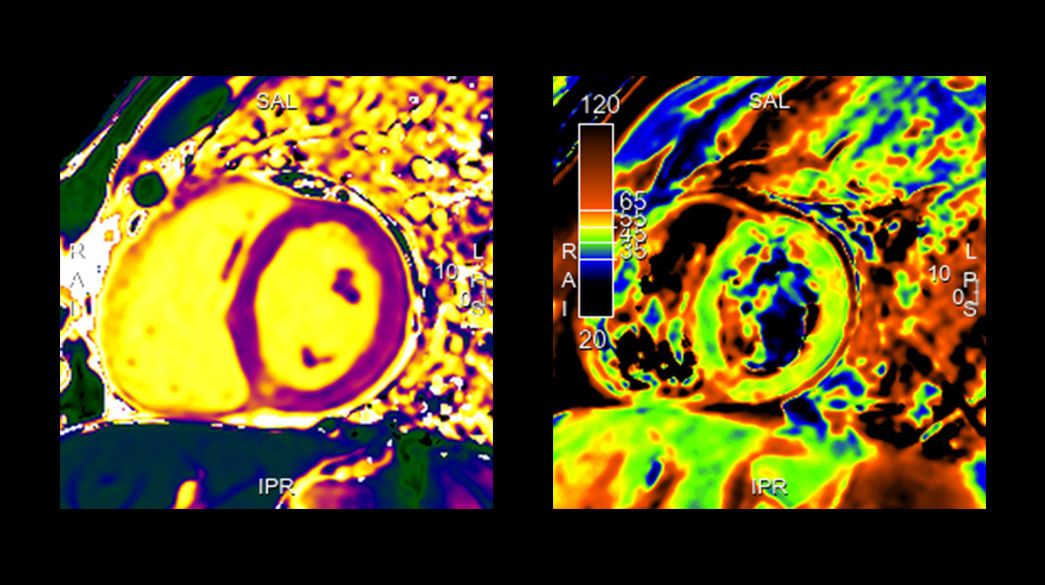

CardioMaps – compatible with AIR™ Recon DL

T1 Mapping as a choice is based on an GE HealthCare exclusive sequence SMART1Map or on an inversion recovery sequence MOLLI

StarMap – compatible with AIR™ Recon DL

A non-invasive technique that evaluates iron overload in the myocardium and liver